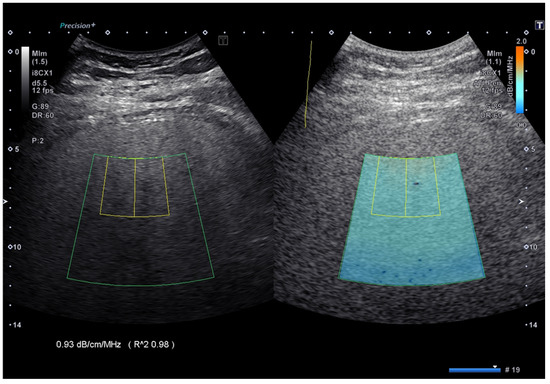

AC measurements were performed with the Aplio i800 US system using the attenuation imaging (ATI) algorithm (Canon Medical Systems, Otawara, Tochigi, Japan). ATI quantifies the AC using a real-time color-coded map (Figure 1).

Figure 1. Attenuation coefficient implemented on the Aplio i-series ultrasound system (Canon Medical Systems, Japan). The attenuation coefficient values are color-coded, allowing the visualization of areas of artifacts and to avoid including them in the measurement box. The reliability of the measurement is displayed as an R^2 value, which is a coefficient of determination, and the best quality of the measurement is obtained with an R^2 ≥ 0.90.